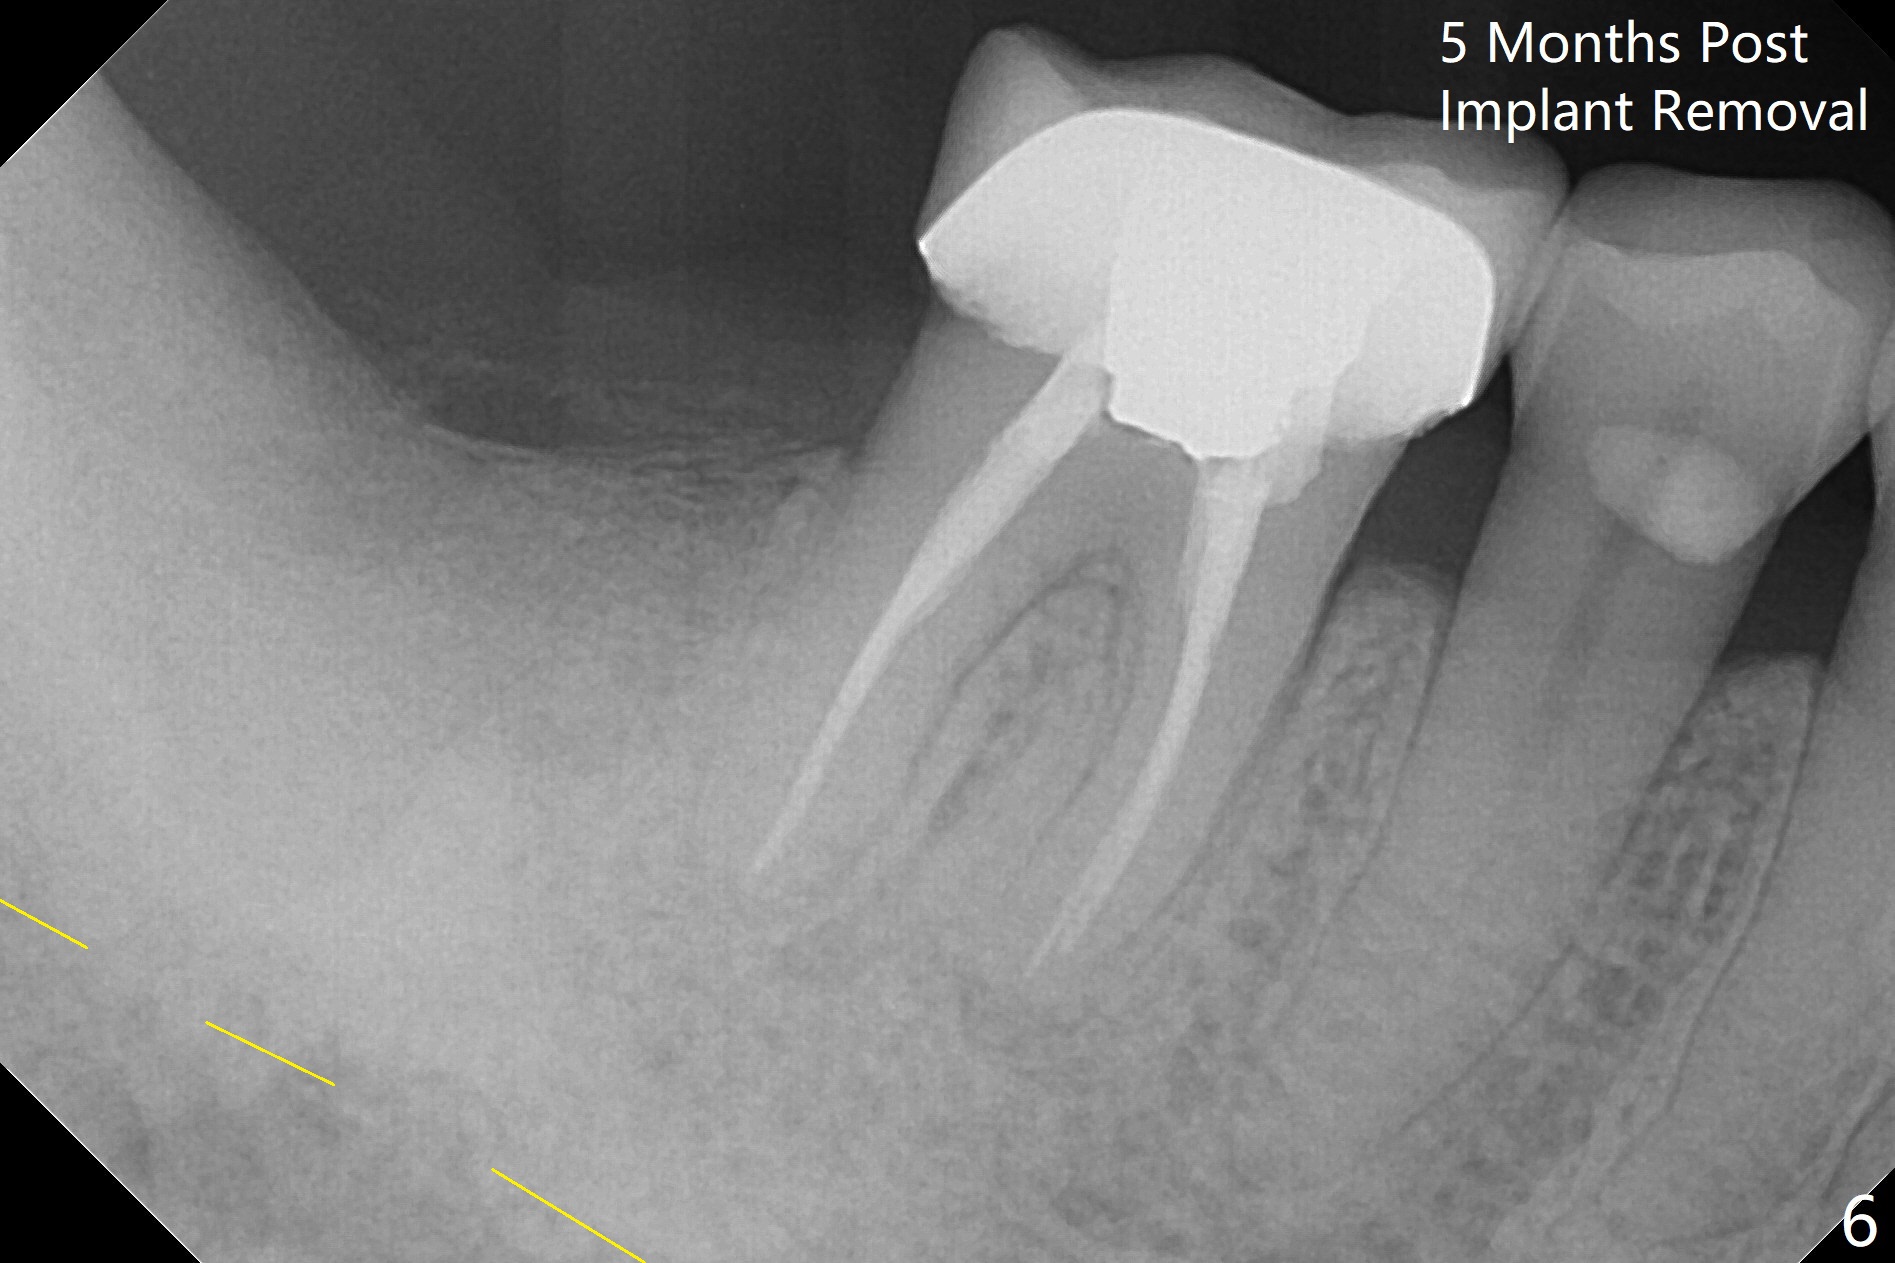

There is a mesiobuccal fistula at #31 with periimplantitis (Fig.1 ^). The bone loss is severe before and after implant removal (Fig.2). It is impossible to place bone-level implant in the original osteotomy due to insufficient bone height. There is pain when a new osteotomy is being initiated in the mesial slope. Following placement of Vera Graft (Fig.3), collagen plug and 6-month resorbable membrane, the wound is closed with suture (mild tension). Postop, there is oozing. Periodontal dressing should have been applied. If the ridge can be preserved in 4-6 months, a 11 mm long implant (Fig.4 green line with 4 mm of the native bone) can be placed with 1.9 mm clearance (red dashed line: the superior border of the Inferior Alveolar Canal); the abutment is estimated to have 4 mm cuff (pink). The socket appears to be healing 8 days postop (Fig.5). The ridge remains wide 5 months post implant removal, although the bone density is low (Fig.6,7 (still ~ 1000 units). It seems that a 5x11.5 mm implant could be placed in the mesiobuccal aspect of the bony defect (Fig.8). For better occlusion, the implant should be shorter (5x8.5 mm) after discussion with the guide lab (Fig.9). Make sure that the most coronal thread is buried by the bone graft, i.e., underneath the crest(>).